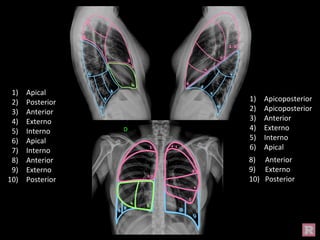

Segmentación Pulmonar (frente)

Apical

Anterior

Externo

Interno

Apicoposterior

Segmentación Pulmonar

(perfil derecho)

Posterior

(perfil izquierdo)

1) Apical

2) Posterior

3) Anterior

4) Externo

5) Interno

6) Apical

7) Interno

8) Anterior

9) Externo

10) Posterior

1) Apicoposterior

2) Apicoposterior